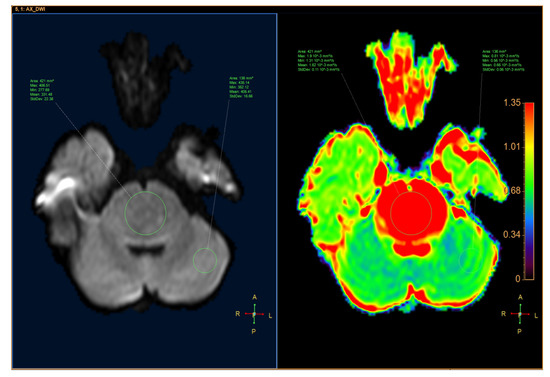

ADC was quantified by defining the region of interest (ROI) for the tumor and the parenchyma on the ADC map with MR Diffusion tool available in Philips Intellispace Portal, version 11 (Philips, Best, The Netherlands). ADC will provide the following parameters: maximum ADC (ADCmax), minimum ADC (ADCmin), mean ADC (ADCmean), and standard deviation ADC (ADCsd). The following additional parameters were also assessed: the ratio of tumor ADCmax to parenchyma ADCmax (rADCmax), the ratio of tumor ADCmin to parenchyma ADCmin (rADCmin), the ratio of tumor ADCmean to parenchyma ADCmean (rADCmean), and the ratio of tumor ADCsd to parenchyma ADCsd (rADCsd) (Figure 1 and Figure 2).

Figure 2.

A 10-year-old male patient had a tumor located in the pons, which was diagnosed as a diffuse glioma. (Left) Axial DWI image. (Right) ADC map.